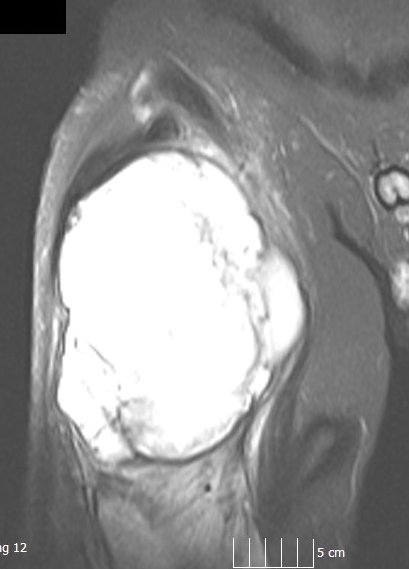

They are usually well seen on an MRI (go here ,here and here).

Patient with a large sarcoma in the right anterior thigh: CT here, MRI here and here, PET after neoadjuvant chemotherapy here and here

MRI Scan